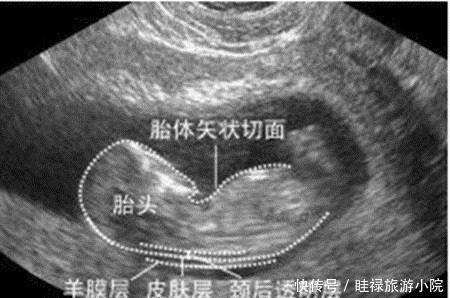

检查时间:怀孕早期到怀孕中期,一般在孕12周产检时检查。这项检查大概在孕11周6天时开始检查,又称为“胎儿颈透明膜厚度的检查”,这项检查对检查时间有严格要求,因而孕妈要提前预约好,按时去做检查。检查方法:通过B超来测量胎儿颈部后方透明膜的厚度,来初步判断胎儿神经管发育的情况,是否存在畸形。如果透明膜过厚,就可能提示:胎儿存在神经管发育的畸形。

京妈建议:① 由于NT检查是最早的关于胎儿智力方面的筛查,因此孕妈一定要严格把控时间做好孕检,及时了解胎儿发育的情况;② NT检查是通过B超来进行的,而且可能是在第一次正规产检时做,不少孕妈会紧张,不过还是建议孕妈尽量避免紧张焦虑,积极配合好医生的检查;③ 如果检查的结果显示:胎儿颈透明膜厚度过厚,孕妈要及时和医生沟通,听从医生的意见。